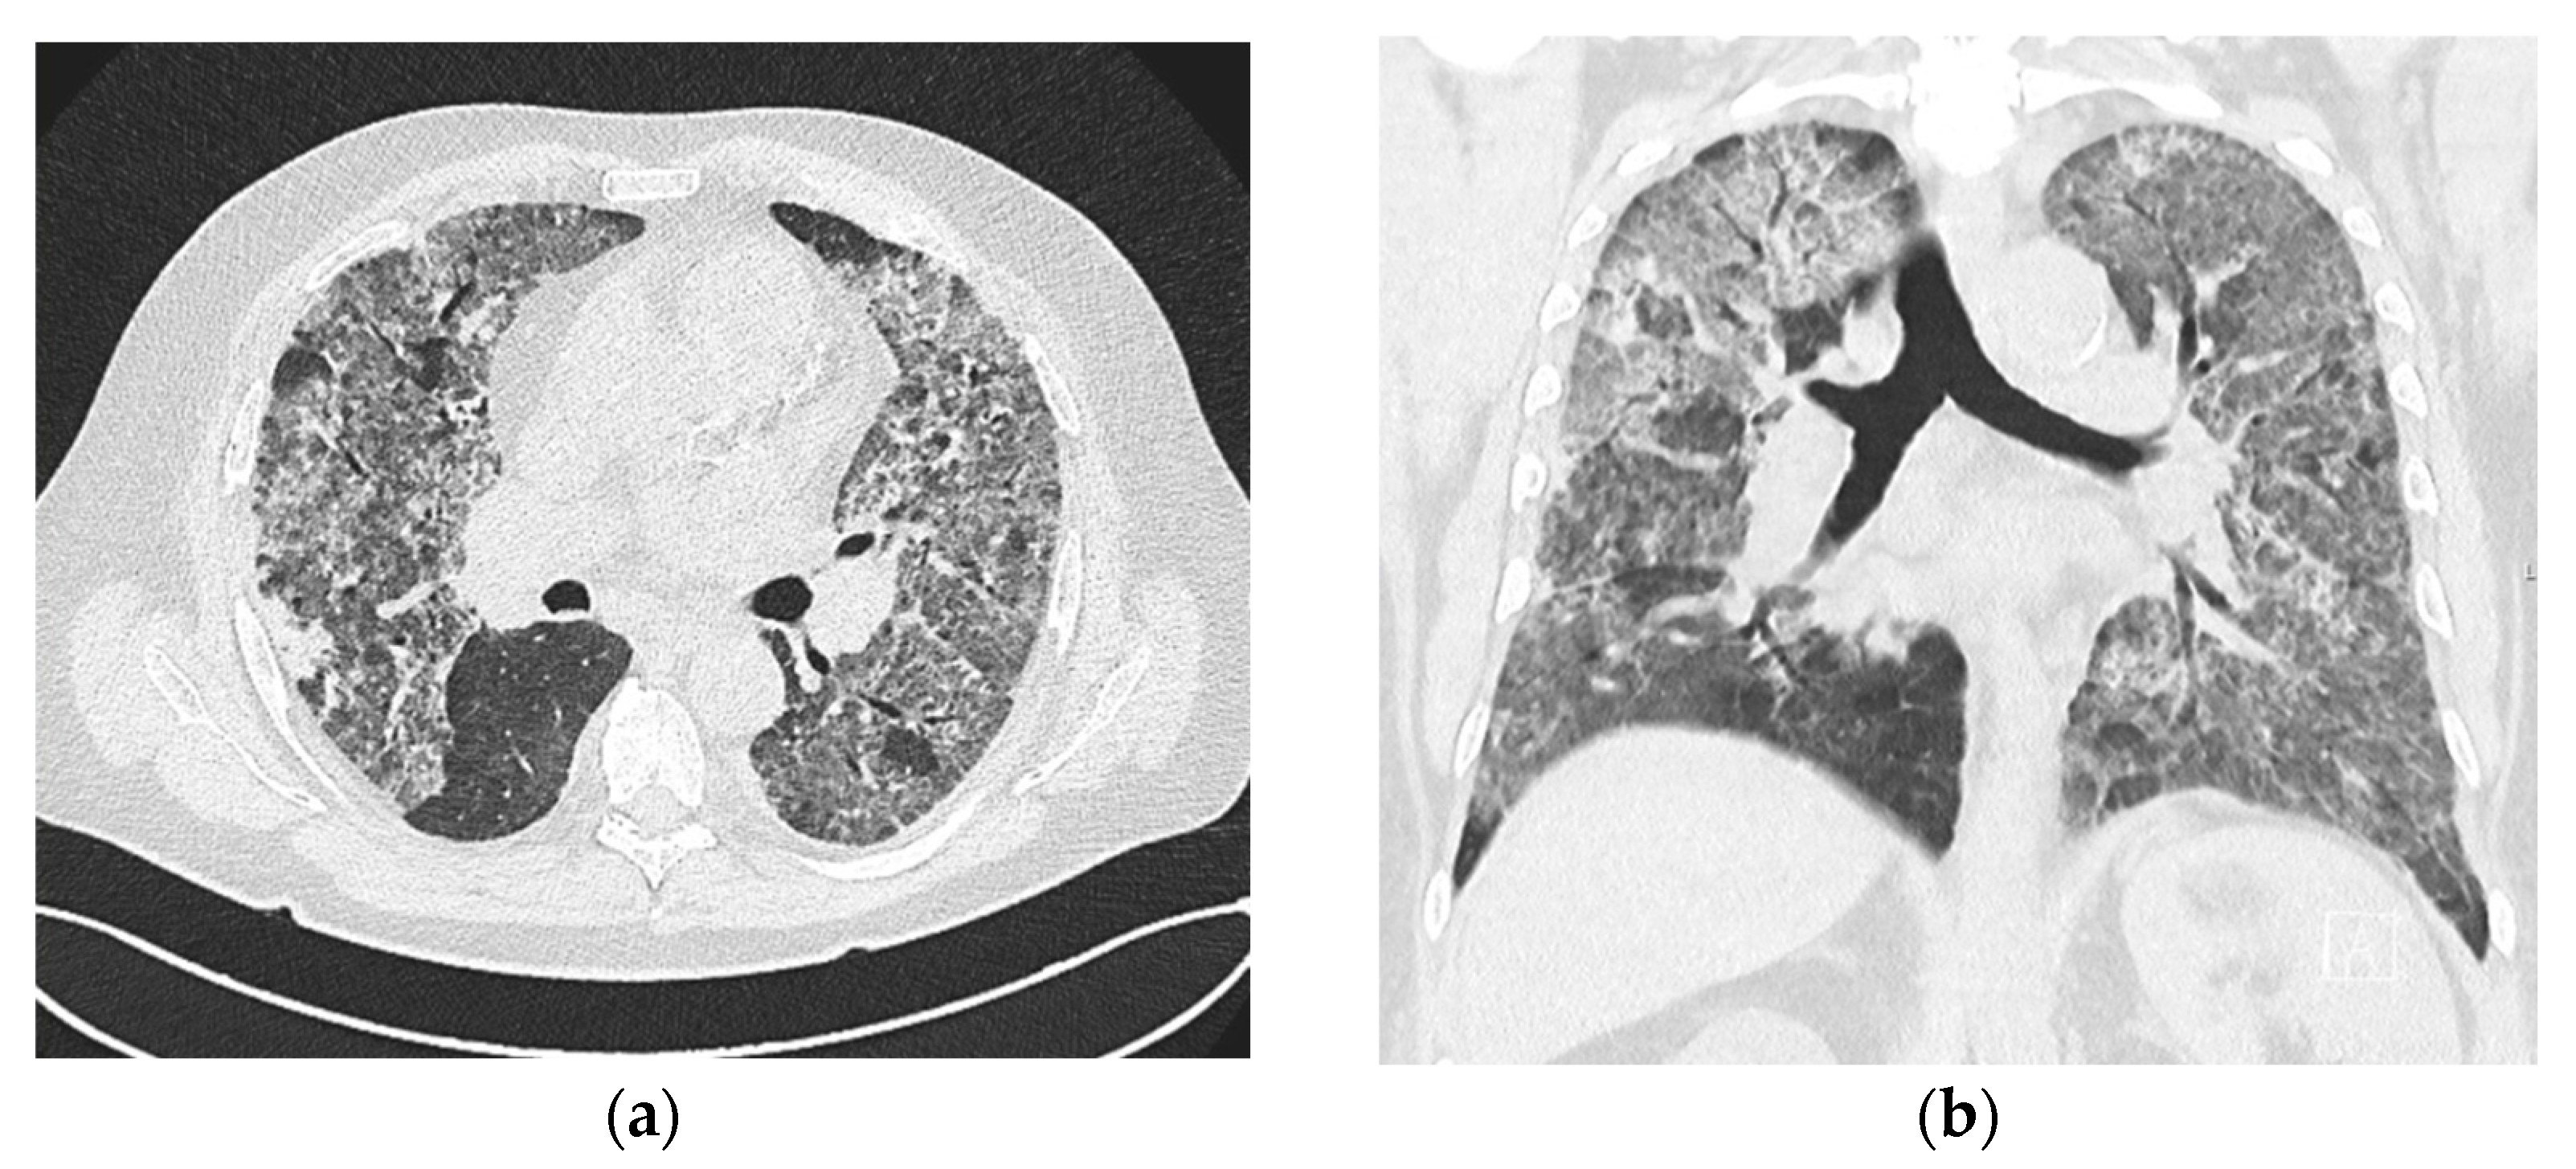

2.1. Case No. 1

2.2. Case No. 2